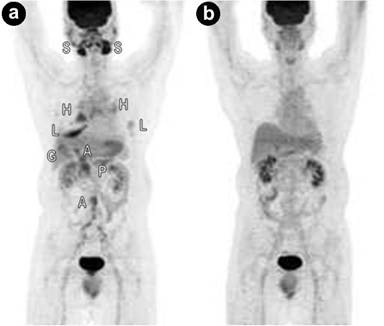

Lymphoma consists of Hodgkin lymphoma (15%) and non-Hodgkin lymphoma (85%). Together, they account for less than 10% of all cancers. Non-Hodgkin lymphoma is more aggressive than Hodgkin lymphoma, having a tendency for extra-nodal involvement. Non-Hodgkin lymphoma makes up of two subtypes: low-grade or aggressive non-Hodgkin lymphoma. Only Hodgkin lymphoma and aggressive non-Hodgkin lymphoma show a high affinity for FDG. An autopsy study showed that up to 30% of non-Hodgkin lymphomas metastasize to the pancreas [11]. Approximately 70% of pancreatic lymphomas respond well to chemotherapy [11]. Current evidence indicates that PET/CT is extremely useful in the staging and restaging of FDG-avid lymphomas (Figure 12). In addition, PET has a prognostic value in lymphoma treatment.

|

Figure 12. a. Fused axial PET/CT image shows a hypermetabolic lesion of non-Hodgkin lymphoma of the pancreas (arrow). The other two bright “spots? represent normal kidney excretion of FDG tracer. b. Corresponding axial CT image (arrow). |